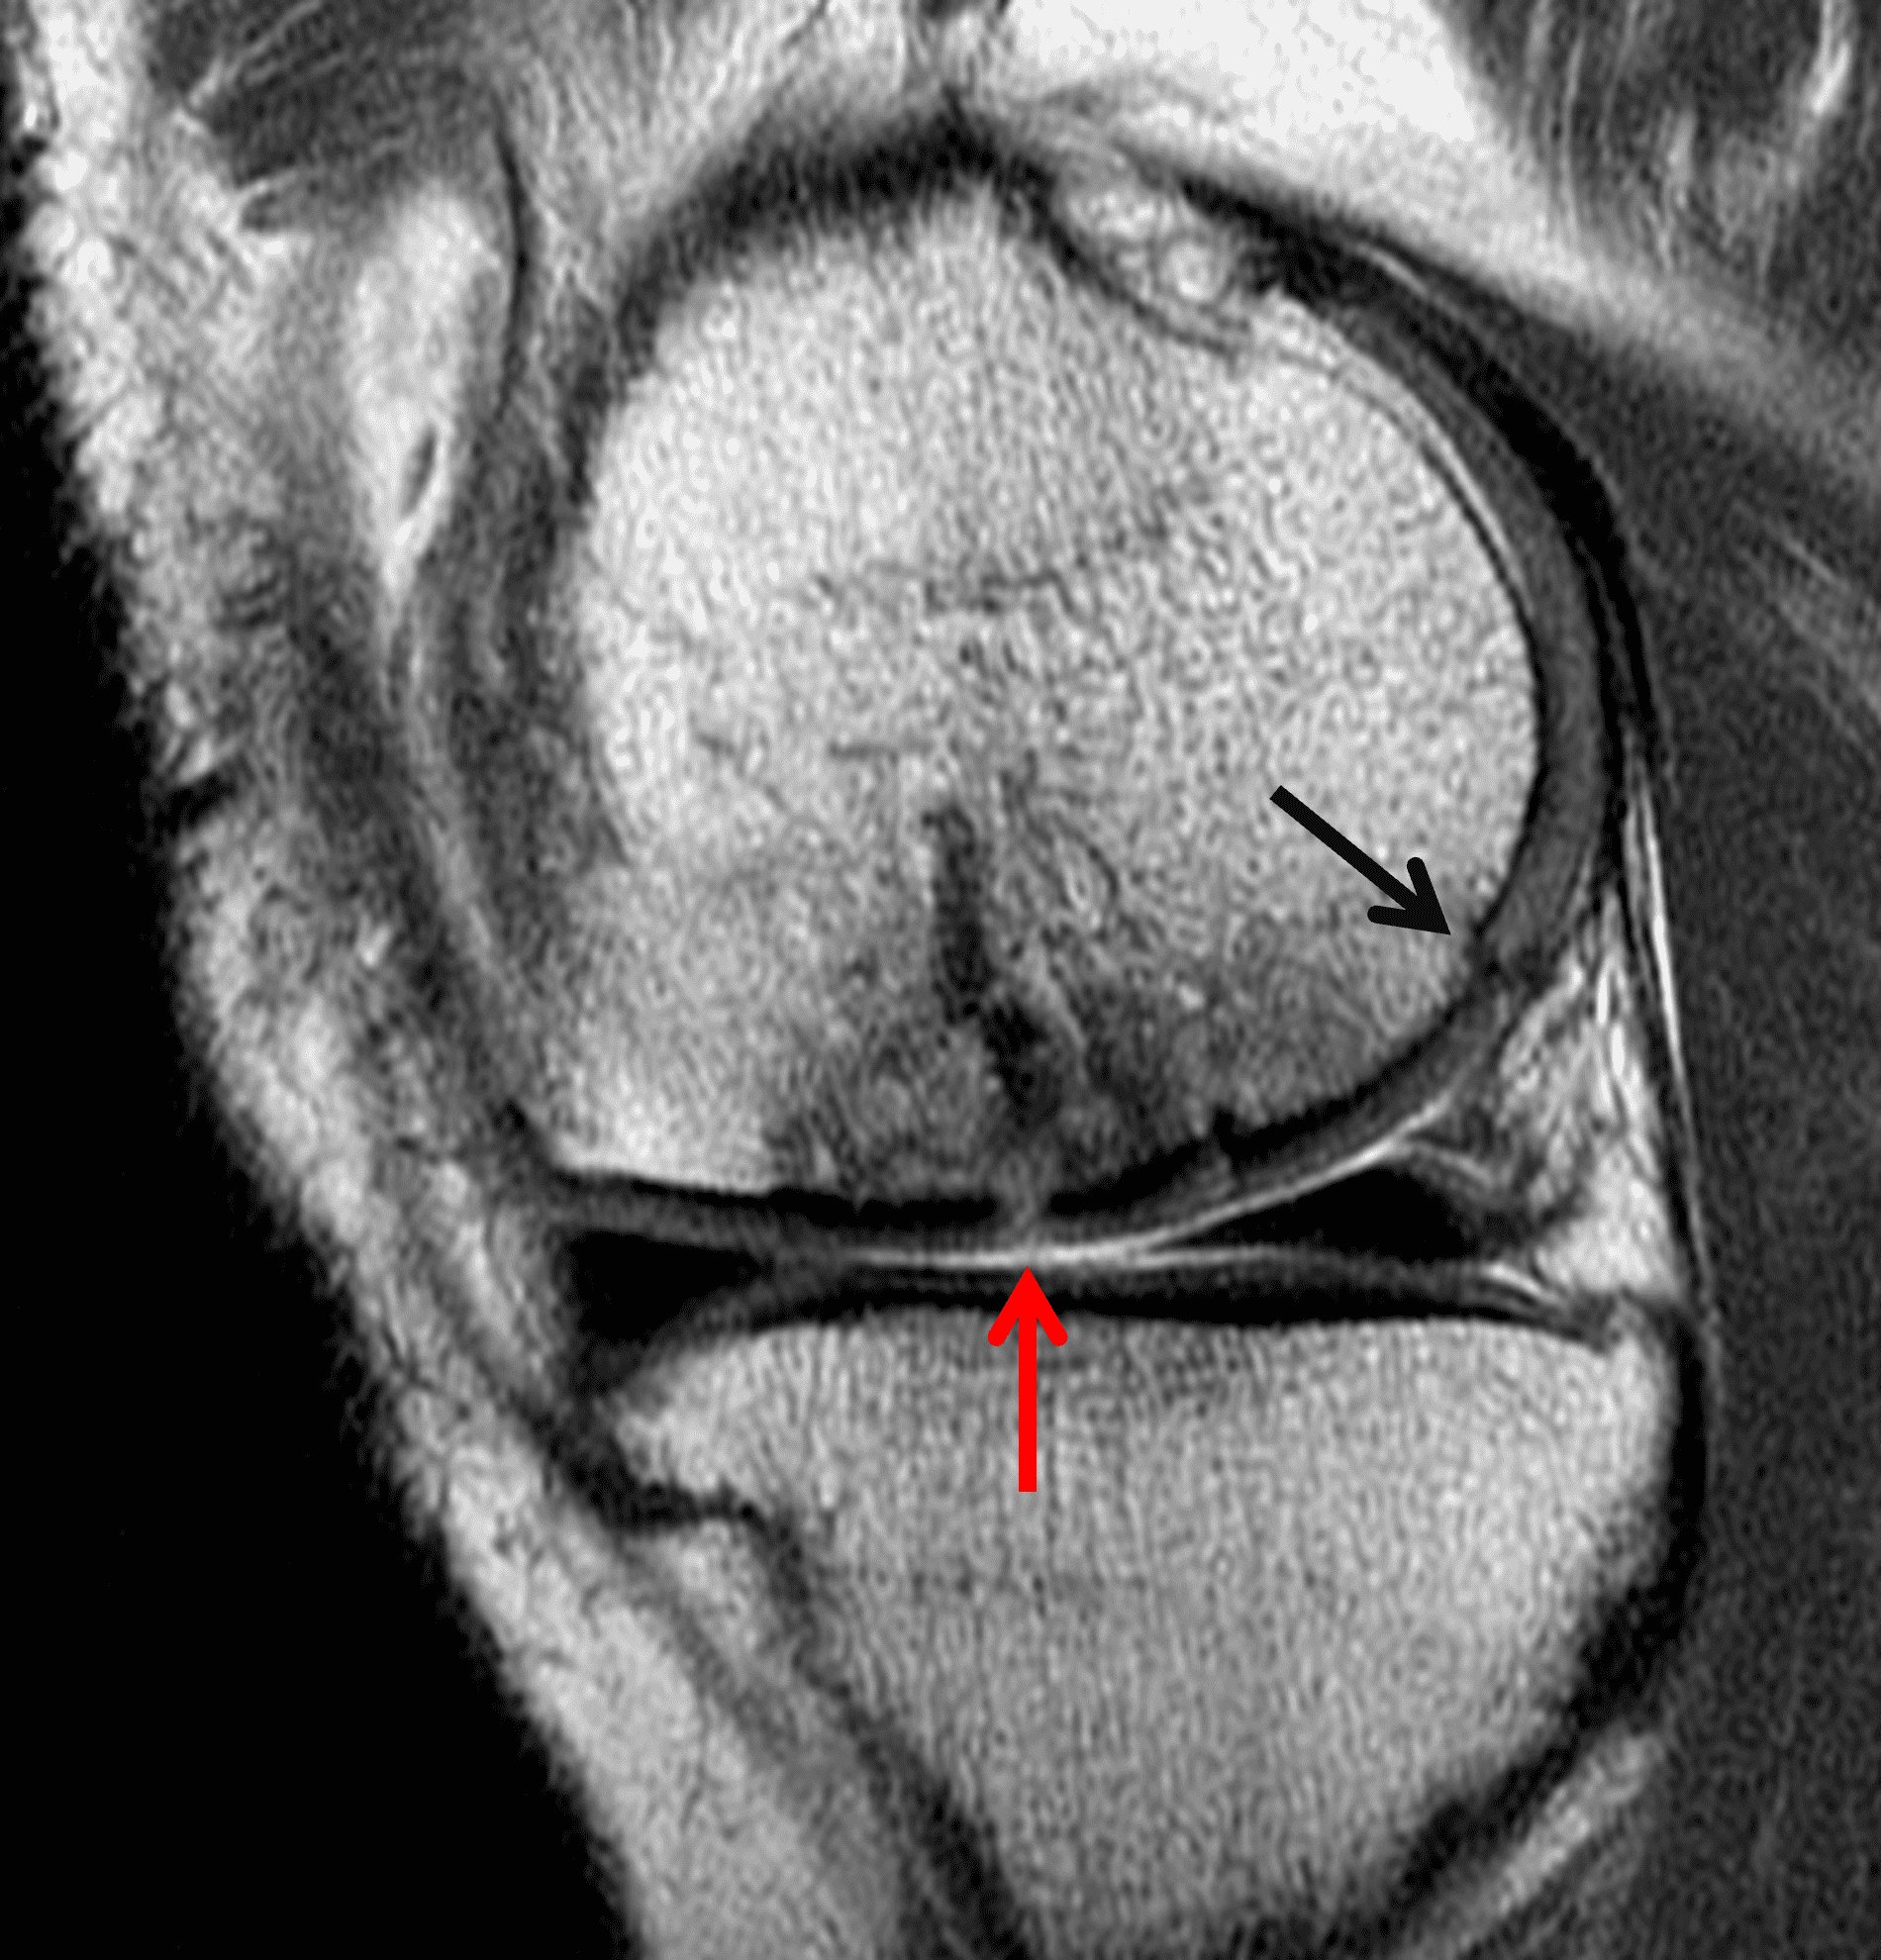

A 32-year-old man suffered a traumatic chondral injury to the medial femoral condyle that was treated with an osteochondral allograft 20 months previously. Representative images from a current knee MRI include (1A) coronal fat-suppressed fluid-sensitive and sagittal (1B) T1-weighted, (1C) proton density-weighted, and (1D) T2-weighted sequences. Are the post-operative MRI findings normal and expected, or abnormal and pathologic? Based on these images, would you characterize the procedure as a success or failure?

Figure 2: (2A) On the coronal image, the margins of the osteochondral graft are faintly visible (arrowheads). Both the graft and underlying bone show mild marrow edema, an expected finding. (2B) The T1-weighted image shows continuity of the marrow in the graft (asterisks) with the underlying bone, indicating osseous integration. A bioabsorbable pin (arrow) used for graft fixation is partly visible. (2C) The proton density-weighted image shows a low signal intensity seam (black arrow) between the native cartilage and transplant, as well as a defect in the subchondral bone plate of the graft (red arrow) where the pin was drilled, both normal findings. (2D) The T2-weighted image shows a smooth, congruent articular surface (arrows), restoring the normal anatomy, and a tiny subchondral cyst. No findings are present to suggest graft failure. The patient’s current symptoms were attributed to pathology elsewhere in the joint (not shown).